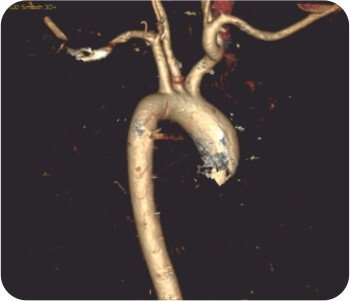

CT thoracic angiograph

CT chest with thoracic angiogram revealed bilateral cavitary lesion with hypertrophied collateral arteries predominantly supplying the right upper lobe cavity. FOB done showed active bleeding from right upper lobe bronchus.

Watanabe sphigot occlusion of anterior subsegment of right upper lobe + glue instillation of right apical and posterior sub segment followed by bronchial artery embolization was done.